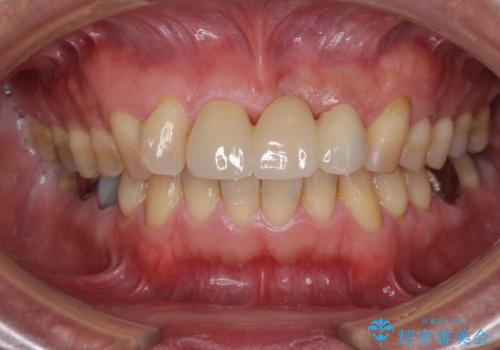

不自然な前歯のブリッジをオールセラミックできれいに

- 保険診療の前歯のブリッジが、形態も色も不自然で気になるとのことで来院された患者様です。

神経の抜かれている土台の歯は根管治療を行った上で、オールセラミックブリッジにより補綴することとしました。

術前の状態より、欠損部位には歯肉移植術が必要と思われましたが、仮歯で調整したところ自然な歯列となったため、外科処置は行わずに自然な口元に仕上がりました。